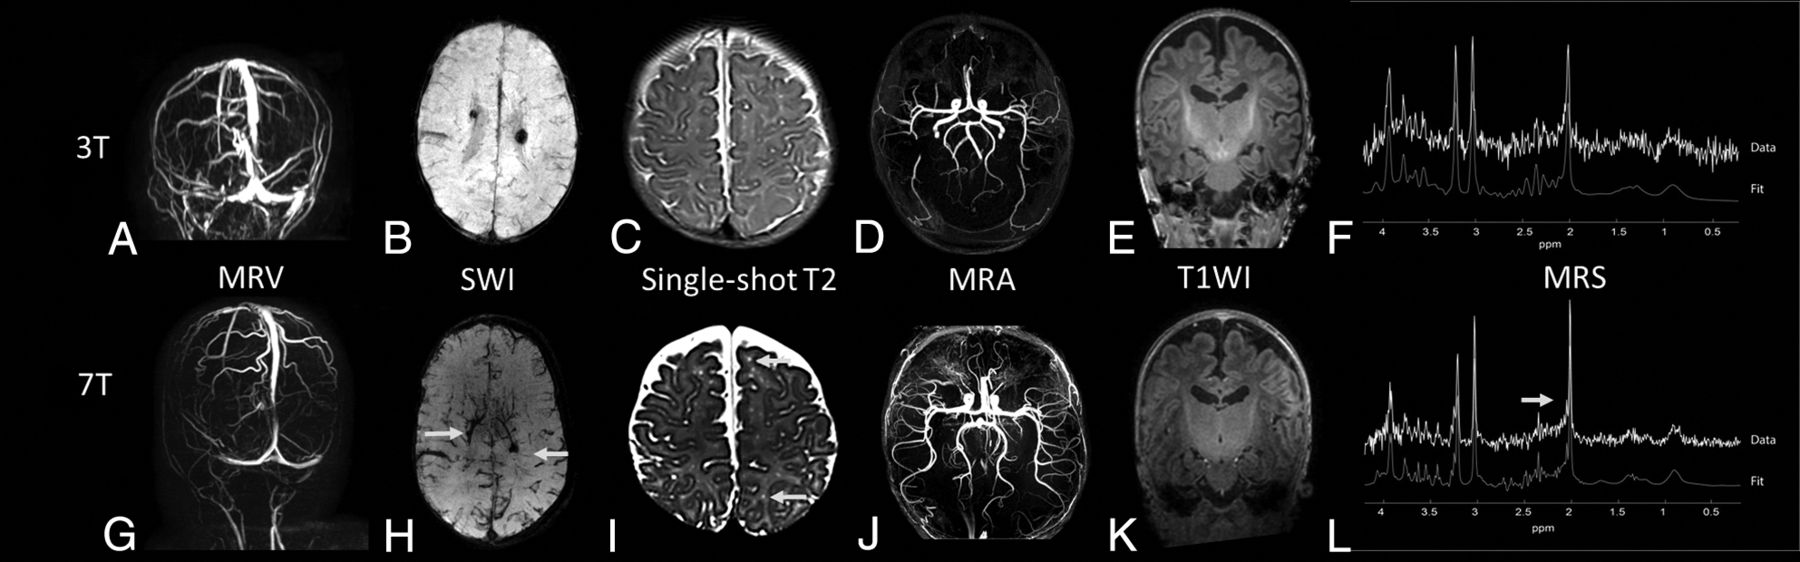

MRV at 7T provided good visibility of the different veins and sinuses: The superficial cerebral veins could be followed in detail (Fig 4A, -G).

Examples of images of different patients at 3T (upper row) versus 7T MR imaging (lower row). A and G , MRV at 3T and 7T, respectively, of a preterm infant at term-equivalent age. B and H, An SWI at, respectively, 3T and 7T of a preterm infant at term-equivalent age. C and I, The 6-week follow-up single-shot T2-weighted image of a term-born infant with a perinatal stroke. The arrows indicate perivascular spaces that were better visualized at 3T compared with 7T. D and J, A 3-month follow-up MRA at 3T and 7T of a term-born infant with an occipital stroke. E and K, T1WI (MPRAGE) of a preterm-born infant at term-equivalent age. F and L, An MR spectroscopy spectrum at 3T and 7T of a preterm infant at term-equivalent age, both with a comparable ROI in the left basal ganglia/thalami region.

Also, SWI at 7T was feasible and showed details of the deep venous circulation, i.e., the deep medullary veins (Fig 4B, -H).

Single-shot T2WI at 7T demonstrated good gray and white matter contrast. In 1 patient with a perinatal arterial stroke, perivascular spaces were seen at 7T that were not visible at 3T (Figs 4C, -I). Otherwise, no clinically relevant additional findings were reported by the pediatric neuro radiologist (M.L.) at 7T. The gray and white matter differentiation at T1WI was suboptimal at 7T (Figs 4E, -K).

MRA showed more peripheral arteries at 7T, and little noise was visible at 7T, making it easier to see the thickness and curves of the arteries (Figs 4D, -J).

MR spectroscopy was of improved quality. For example, the patient shown in Fig 4F, -L had an SNR of 19 at 7T compared with 6 at 3T. It was possible to correctly fit more metabolites with a Cramer–Rao Lower Bound of <20% at 7T, such as N-acetyl aspartylglutamate, taurine, and glycine.